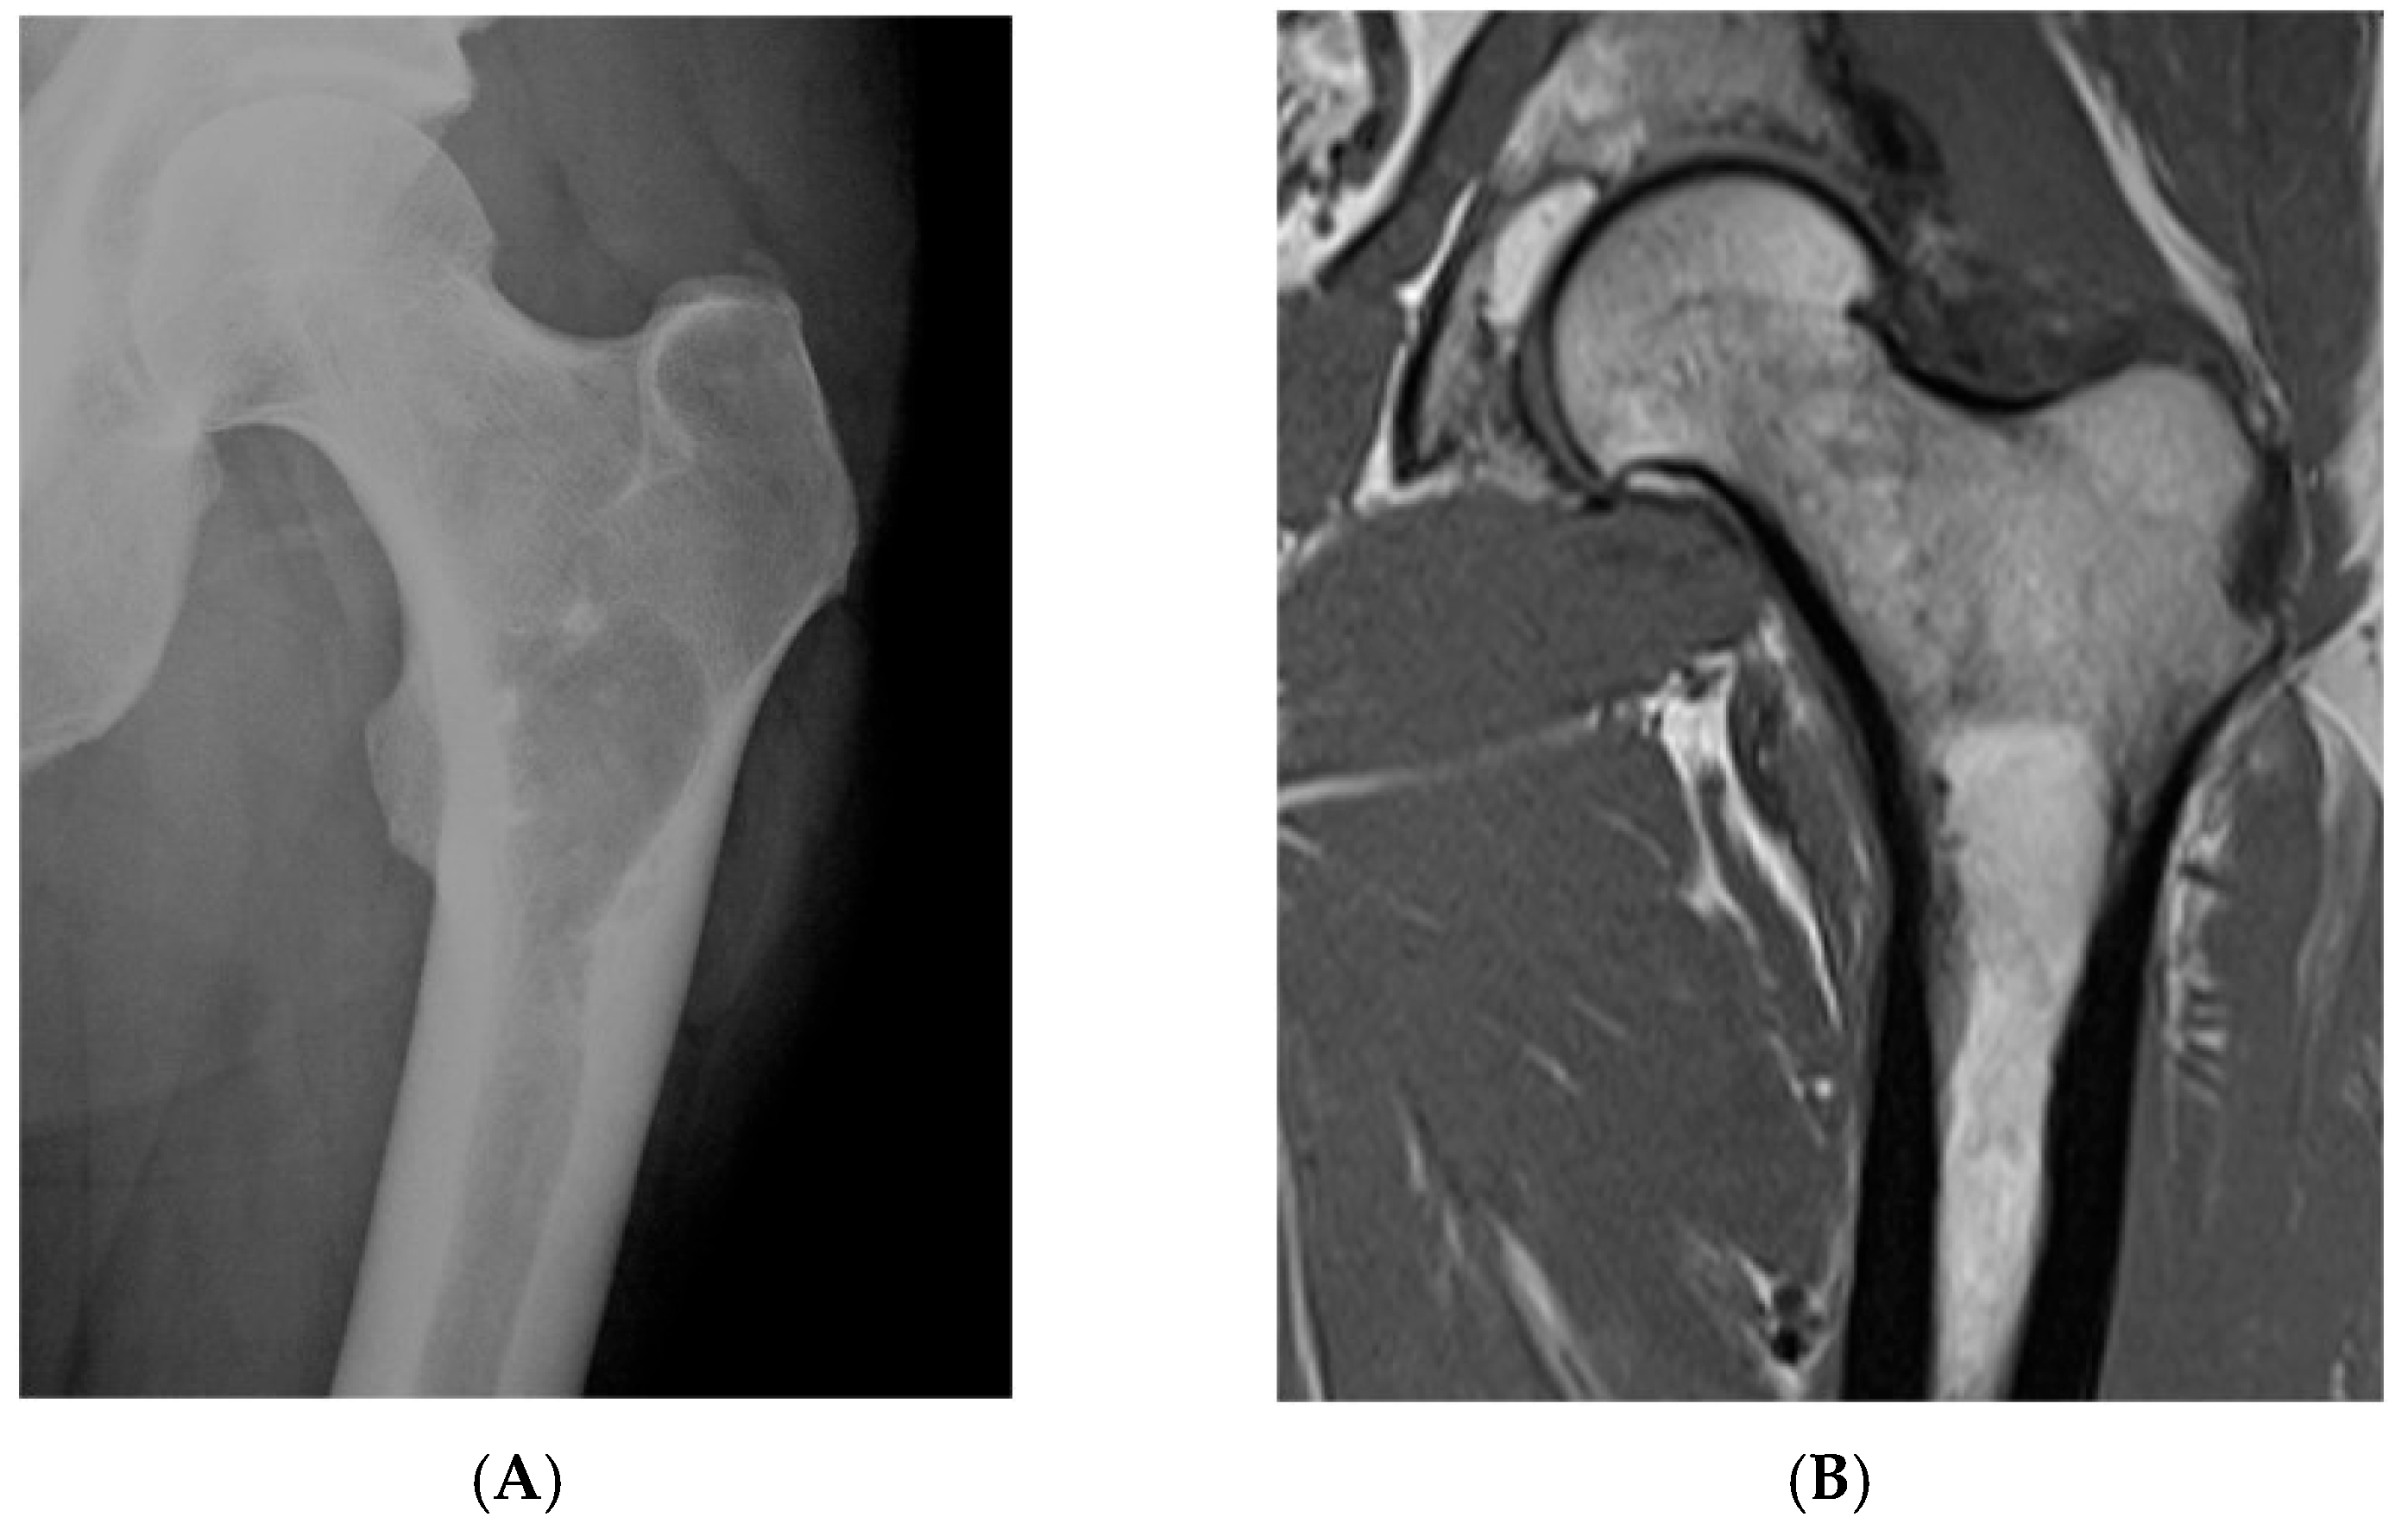

Figure 1.

Intraosseous lipoma, left proximal femur. (A) AP radiograph proximal femur depicting well-defined, lucent bone lesion. (B) Coronal T1W MRI depicting fat-containing lesion. (C,D) Axial MRI T1W and STIR (respectively) demonstrating fat content without and with fat suppression.